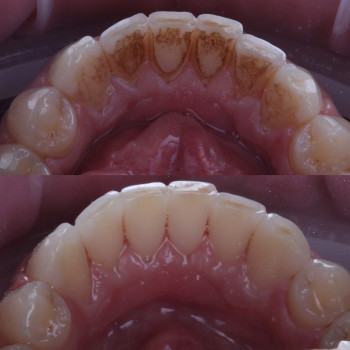

Лікування пародонтиту від 1 до 4 ступеня тяжкості у Хмельницькому Пародонтит – це запальне захворювання ясен і тканин, що утримують зуби. Без лікування воно прогресує від початкового нальоту й кровоточивості до серйозної втрати кісткової тканини та рухливості зубів. У нашій клініці ми проводимо комплексне лікування пародонтиту будь-якої стадії – від 1 до 4 ступеня тяжкості. ✔️ 1 ступінь – професійна гігієна, усунення нальоту, навчання догляду ✔️ 2 ступінь – кюретаж ясенних кишень, лікування запалення ✔️ 3 ступінь – комплексна терапія, шинирование, відновлення тканин ✔️ 4 ступінь – хірургічні методи, імплантація та протезування при втраті зубів Ми використовуємо сучасні методи: ультразвукову чистку, Air Flow, закритий кюретаж. Регулярне звернення до пародонтолога дозволяє зупинити прогресування хвороби, зберегти власні зуби та повернути здоров’я ясен. 👉 Запишіться на консультацію та лікування пародонтиту у Хмельницькому – відновіть здоров’я ротової порожнини на будь-якій стадії захворювання!